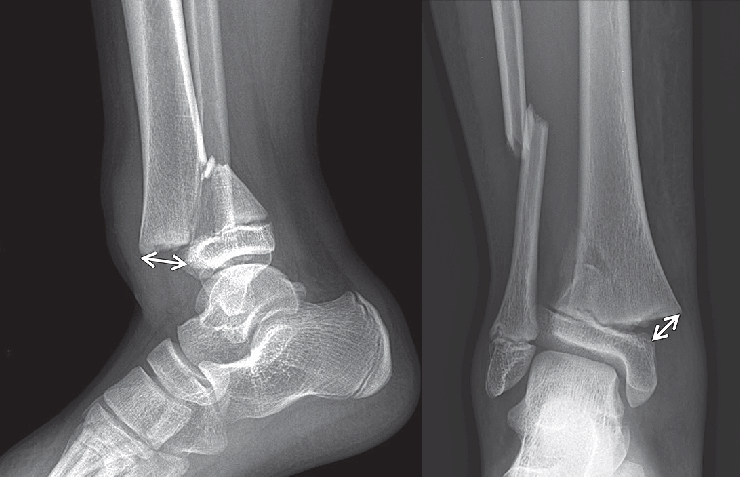

Рентген обычно используется для оценки переломов и оценки степени смещения и нестабильности.Дополнительные визуализирующие исследования, такие как КТ или МРТ, могут быть рекомендованы для получения более подробной информации о характере перелома, поражении мягких тканей и качестве кости.

Операция с блокирующей пластиной часто рекомендуется при сложных переломах, которые представляют собой переломы, включающие множественные костные фрагменты или связанные с повреждением мягких тканей.Эти переломы сложнее лечить консервативными методами и требуют стабильности, обеспечиваемой блокирующими пластинами.

Переломы несущих костей, таких как бедренная или большеберцовая кость, могут потребовать хирургического вмешательства с блокирующей пластиной.Эти кости подвергаются значительной нагрузке во время повседневной деятельности, а хирургическое вмешательство при стопорные пластины может помочь восстановить прочность и стабильность кости, что позволяет проводить раннюю мобилизацию.